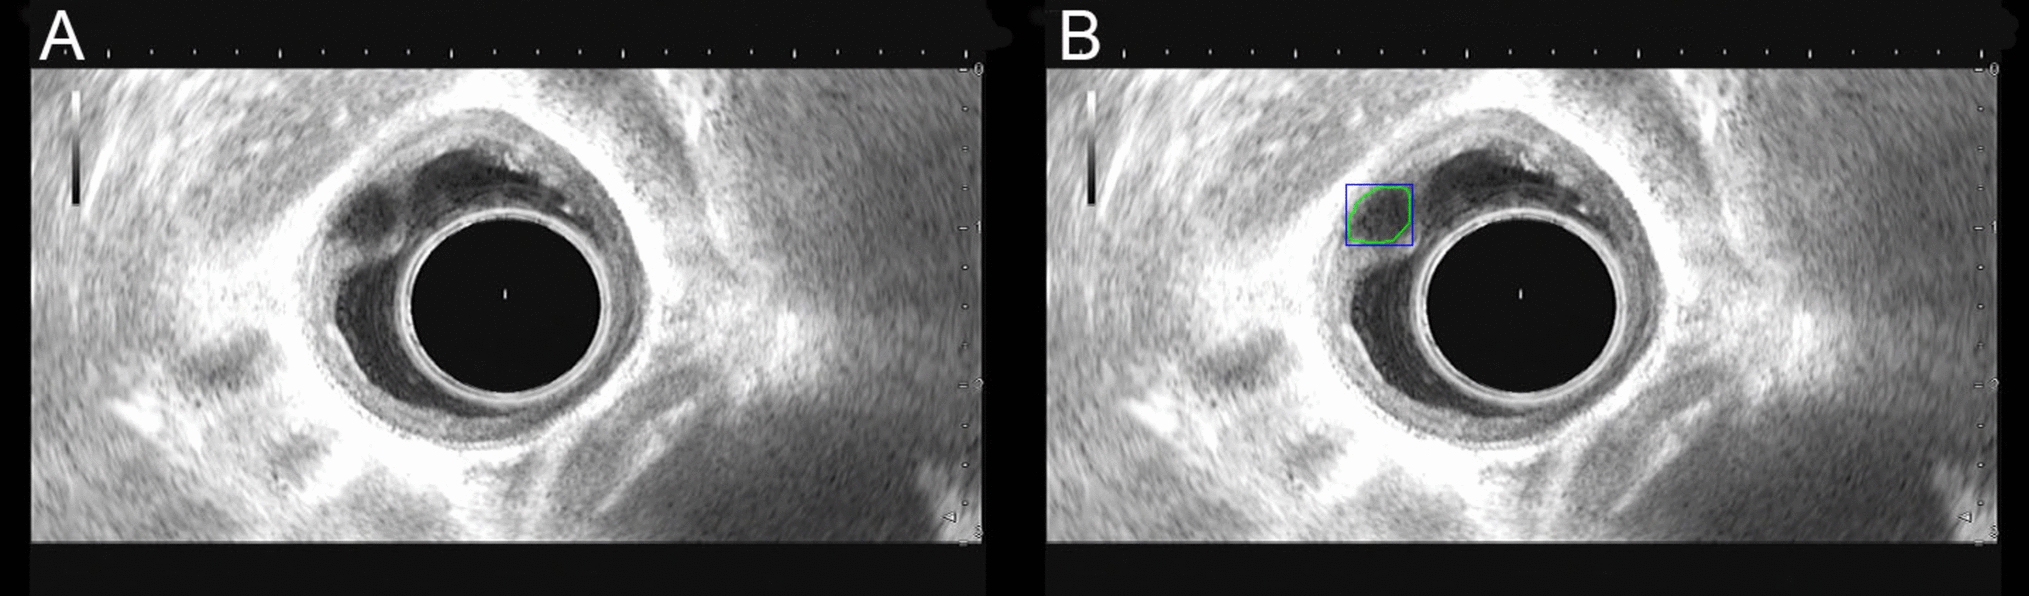

The precision of the lesion location detection was 92.2% (95%CI, 87.0–95.3%), the recall was 73.6% (95%CI, 66.1–79.5%), mAP@0.5 was 0.832, and F1-score was 81.9% (95%CI, 75.2–87.0%). Figure 4 shows an example of esophageal SEL recognition using an EUS-AI image model.

Fig. 4

Example of test set image labeling. A Representative image of esophageal SELs. B AI model recognition image. The green frame indicates the diagnosis by the AI system. SEL subepithelial lesion, EUS endoscopic ultrasound

The EUS-AI model illustrated an accuracy of 73.6%, which was similar to the senior endoscopists’ range of (71.5–80.6%) (P = 0.146). In contrast, the accuracy was significantly greater than that of junior endoscopists (61.8–65.5%, P = 0.041) (Table 3).